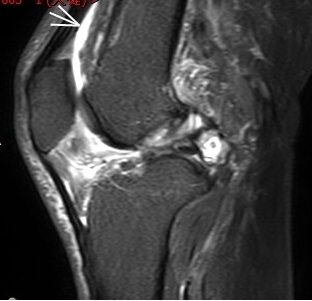

1. “咯吱響”+“卡頓感”——半月板的“碎玻璃警報(bào)”

場(chǎng)景:下蹲時(shí)膝蓋“咯噔”彈響,起身像被“卡住”

MRI偵查:精準(zhǔn)捕捉半月板撕裂或變性(半月板內(nèi)高信號(hào)),避免拖成“關(guān)節(jié)交鎖”

(半月板撕裂)